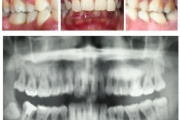

Agressiivne parodontiit

Seda parodontiidi vormi esineb umbes1%-l elanikkonnast. On haiguse kiiresti progresseeruv vorm, mille puhul patsiendid kaotavad kõik hambad enne30-35. eluaastat. Tavaliselt haigestutakse piimahammaste lõikumise ja puberteedi vahele jääval perioodil. Jagunemine:- lokaliseeritud agressiivne vorm- Loe edasi »